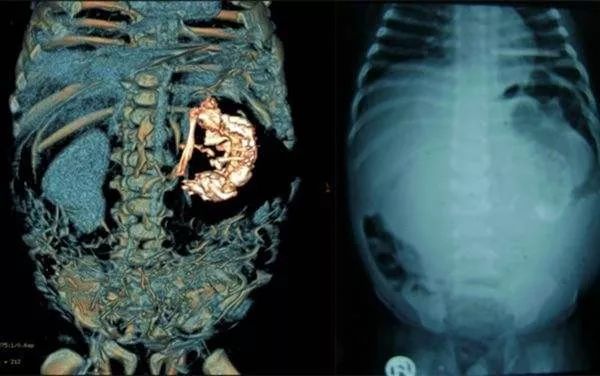

一岁半的小女孩,却莫名其妙的腹大如鼓。多方排查,方知竟是藏在她肚子里的“胎儿”在作祟。罕见的是,依靠掠夺她的营养,这个“胎儿”还发育出了毛发、骨骼等组织,面部骨骼轮廓也清晰可见。

刘修恒、程凡两位专家联手手术,于卿卿腹腔内发现了一直径约为20公分的巨大肿瘤。从中抽取出600余毫升的白色粘液后,才将肿瘤顺利取出。医生将瘤体切开,却意外发现一个类似胚胎的组织,其中还有毛发、骨头等物质,头骨上面还有两个眼窝。

医生推断,这是一个罕见的寄生胎,瘤体其实是一个发育不全的胎儿。幸运的是,揪出这一祸首后,卿卿已恢复健康,痊愈出院。